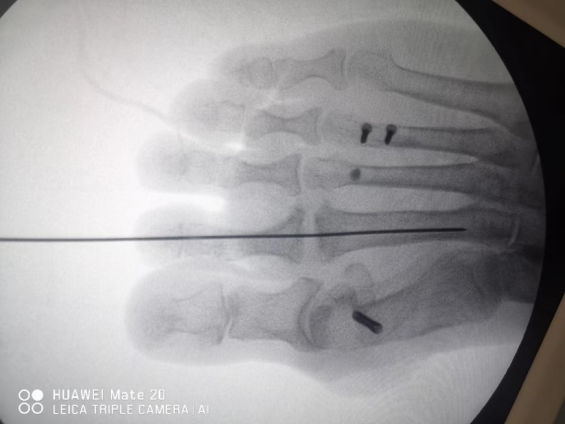

跖骨头背侧闭合楔形截骨术:由于近节趾骨的碰撞导致跖骨头背侧及上方的软骨面受累,跖侧关节面完好者。背侧作3-5cm的纵行切口,暴露跖骨头跖骨颈,关节内清创(避免过度清创,影响跖骨头血运),在背侧用摆锯于跖骨颈水平楔形截骨,跖骨头向近侧和背侧旋转,角度以将跖骨头正常跖侧部分带向背侧为度,尽量维持跖骨长度。交叉克氏针固定6周。并发症:转移性跖痛症;合并骨性关节炎的病例也取得良好疗效。在远端正常跖骨背侧行闭合楔形截骨,将跖骨头正常的跖侧部分翻向背侧,与趾骨关节面相对应。楔形截骨角度尽量维持跖骨长度,除了旋转外不要去除病变。,如果,跖骨头关节面彻底破坏,跖侧无足够的可用来重建关节面的软骨,已经形成终末期关节炎的患者,关节成形术或关节置换术,也是比较好的选择。多中心研究证明,即便4期的病变,术中探及背侧广泛关节面塌陷,但探查发现跖侧仍有足够关节软骨可供翻转上来重建关节面

我们的病例跖骨头背侧闭合楔形截骨术